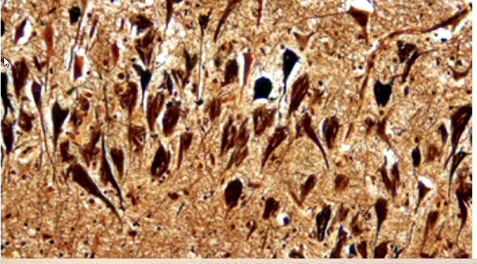

What are we looking at?

neurofibrilary tangles - flame shape or globose tangles